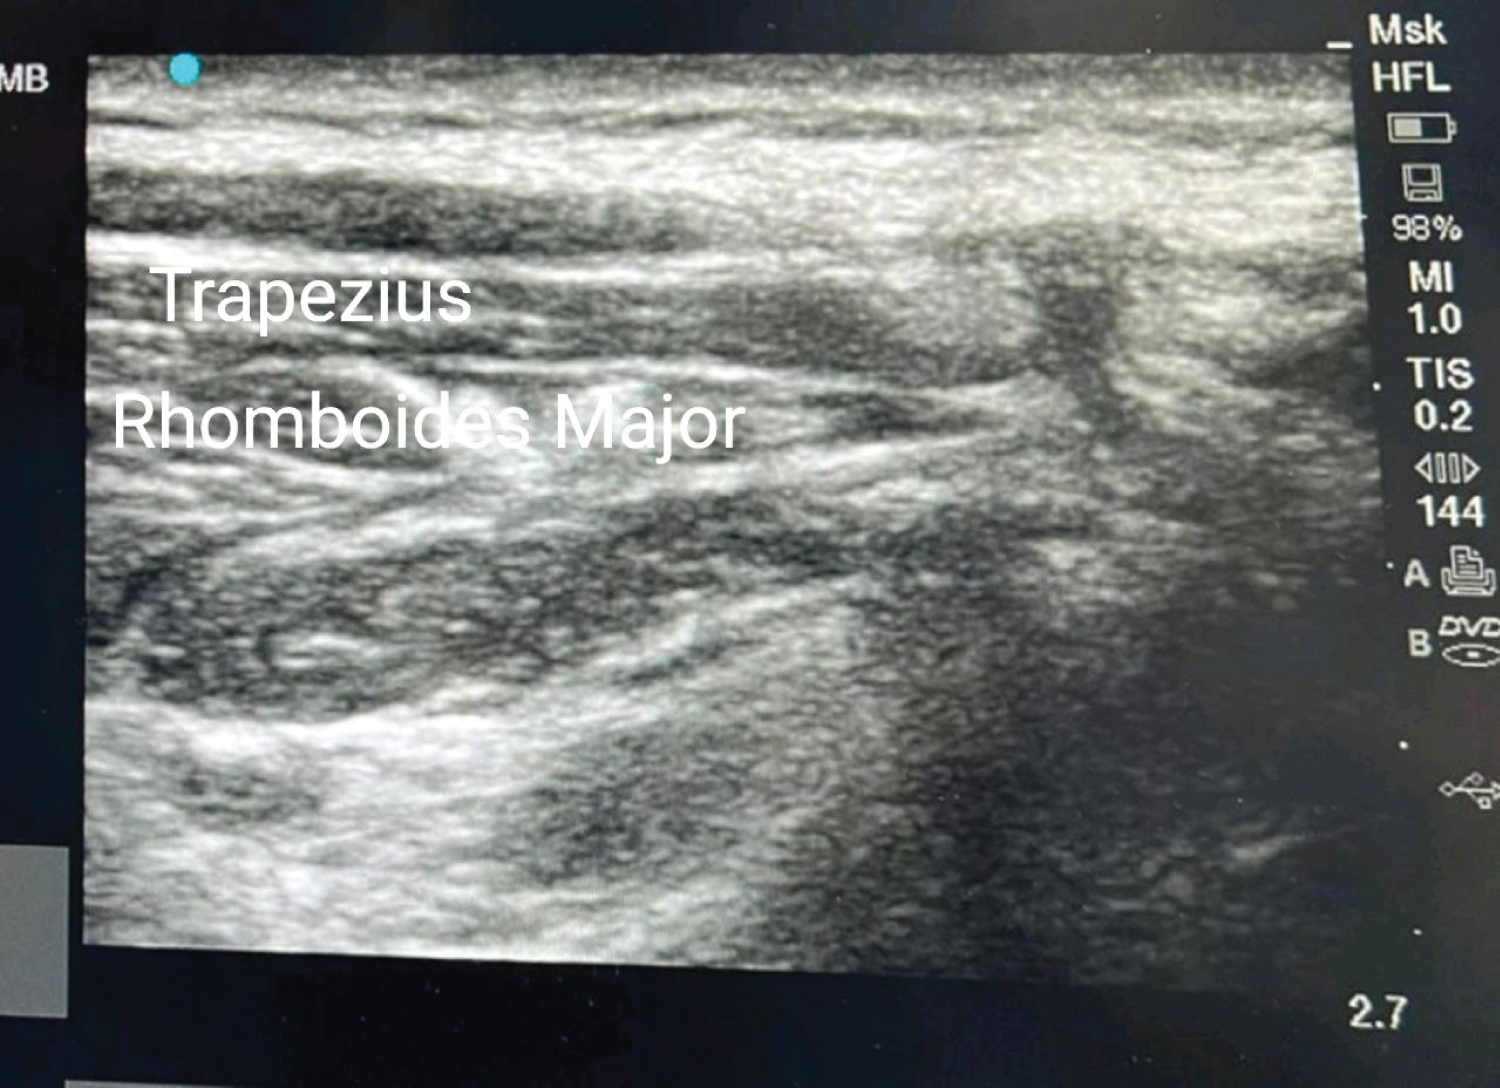

A 27-year-old male, weighing 68 kg patient sustained a pan right brachial plexus injury following a road traffic accident 10 months back. The patient had motor weakness in the right upper limb with a power of 0/5 in the right shoulder, elbow, wrist and fingers. The patient was unable to perform shoulder abduction, adduction and external rotation. The primary goal of the surgery was to restore function in the right shoulder and a nerve transfer of the right Spinal Accessory nerve to the right Suprascapular nerve was planned. The patient did not have any other concomitant injuries and was free from chronic illness and was categorized under American Society of Anaesthesiology (ASA) physical status 2. He complained of pain over the right upper limb ever since the accident, which was burning in nature, associated with numbness and tingling, which was poorly controlled on over-the-counter analgesics. His pain was 5/10 on the numerical rating scale and the Self-Assessment Leeds Assessment of Neuropathic Symptoms and Signs (S-LANSS) Pain Scale was more than 12. In the operating room, ASA standard monitors and Bispectral Index (BIS) monitoring were attached. General anaesthesia was induced using the following medications, Inj. Glycopyrrolate 0.2 mg Intravenous (IV), Inj. Midazolam 1 mg IV, Inj. Fentanyl 70 mcg IV followed by Propofol infusion was initiated with a Target control infusion pump using the Marsh protocol, with a target plasma concentration of 4 mcg/ml. Simultaneously pre-oxygenation was done with 100% oxygen and following a loss of consciousness and a BIS of 40, Inj. Succinylcholine 100 mg IV was administered, and a cuffed endotracheal tube was placed. The patient was put on a volume-controlled mode of ventilation with tidal volume 420 ml, frequency 12 per minute and Positive End Expiratory Pressure (PEEP) 4 hPa. The patient was then placed in the prone position. Thereafter, a right-sided trapezius plane block with 0.2% Ropivacaine 20 ml and Dexamethasone 4 mg was given under ultrasound guidance (Figure 1). Propofol infusion was continued, and the target plasma concentration was titrated between 3 mcg/ml to 4 mcg/ml based on the hemodynamic parameters and a target BIS of 40-60. Intraoperatively, the parameters noted were heart rate, non-invasive blood pressure, SpO 2 and BIS. An incision was given for the posterior/dorsal approach to the spinal accessory nerve as shown in Figure 2A. The suprascapular area was dissected, the supraspinatus ligament was identified (Figure 2B) and the right suprascapular nerve was isolated. Thereafter, a peripheral nerve stimulator was employed for precise identification of the spinal accessory nerve. A current of 3.5 mAmp was delivered to the nerve, and twitches were noted in the trapezius muscle, indicating that the fascial plane block administered did not interfere with the use of the nerve stimulator intraoperatively. The intraoperative course was uneventful, and the hemodynamics remained within 20% of the patient’s baseline (Figure 3). The total duration of surgery was 3.5 hours, thereafter the patient was weaned from mechanical ventilation and shifted to the post-anesthesia care unit. The Numerical Rating Scale (NRS) score at 1-hour postoperative period was 1 and at 6 hours postoperative period was 2. The analgesia plan included intravenous acetaminophen 1 gram eight hourly, Tab pregabalin + nortryptomer (75/10 mg) at bedtime and 50 mg of tramadol IV for breakthrough pain. The time to first rescue analgesia was 14 hours. The cumulative dose of tramadol required in the first 72 hours of surgery was 200 mg. The patient was discharged on the 5 th postoperative day and was enrolled in a neurorehabilitation program at our Centre and is presently being managed on an outpatient basis.

Figure 1: Ultrasound image showing the different layers of tissue for the trapezius plane block. View Figure 1